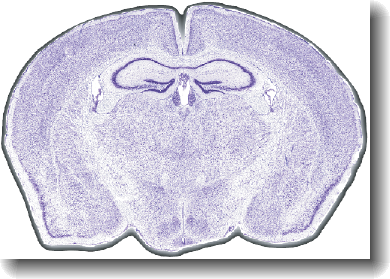

(Circa 2002) MiceSlice produces ultra high-resolution digital brain sections for standardized preparation of brain section tissues. Microscope image tiles are seamlessly reassembled into one brain section and then rotated to perfect alignment. This provides the foundation material for development of standardized experimental protocols.

MiceSlice provides ultra-high resolution digital brain sections from the standardized preparation of brain section tissues. Microscope image tiles are seamlessly reassembled into one brain

section and rotated to perfect alignment. MiceSlice provides the foundation material for the development of standardized experimental protocols. The rigorous quality control applied to

MiceSlice technology makes this the "gold standard" in histological preparations of rodent brain tissue.